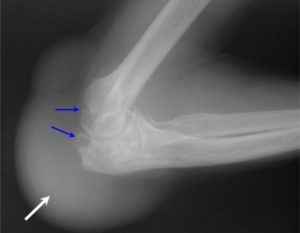

Поскольку новообразование разрастается за счет наружного хрящевого слоя, его внутренняя структура постепенно минерализуется и приобретает характеристики костной ткани. На рентгеновских снимках экзостоза у ребенкачетко видны очертания окостеневшего тела нароста, слившегося с телом кости. При этом хрящевой слой не оставляет тени на рентгенограмме, как и обычный хрящ.